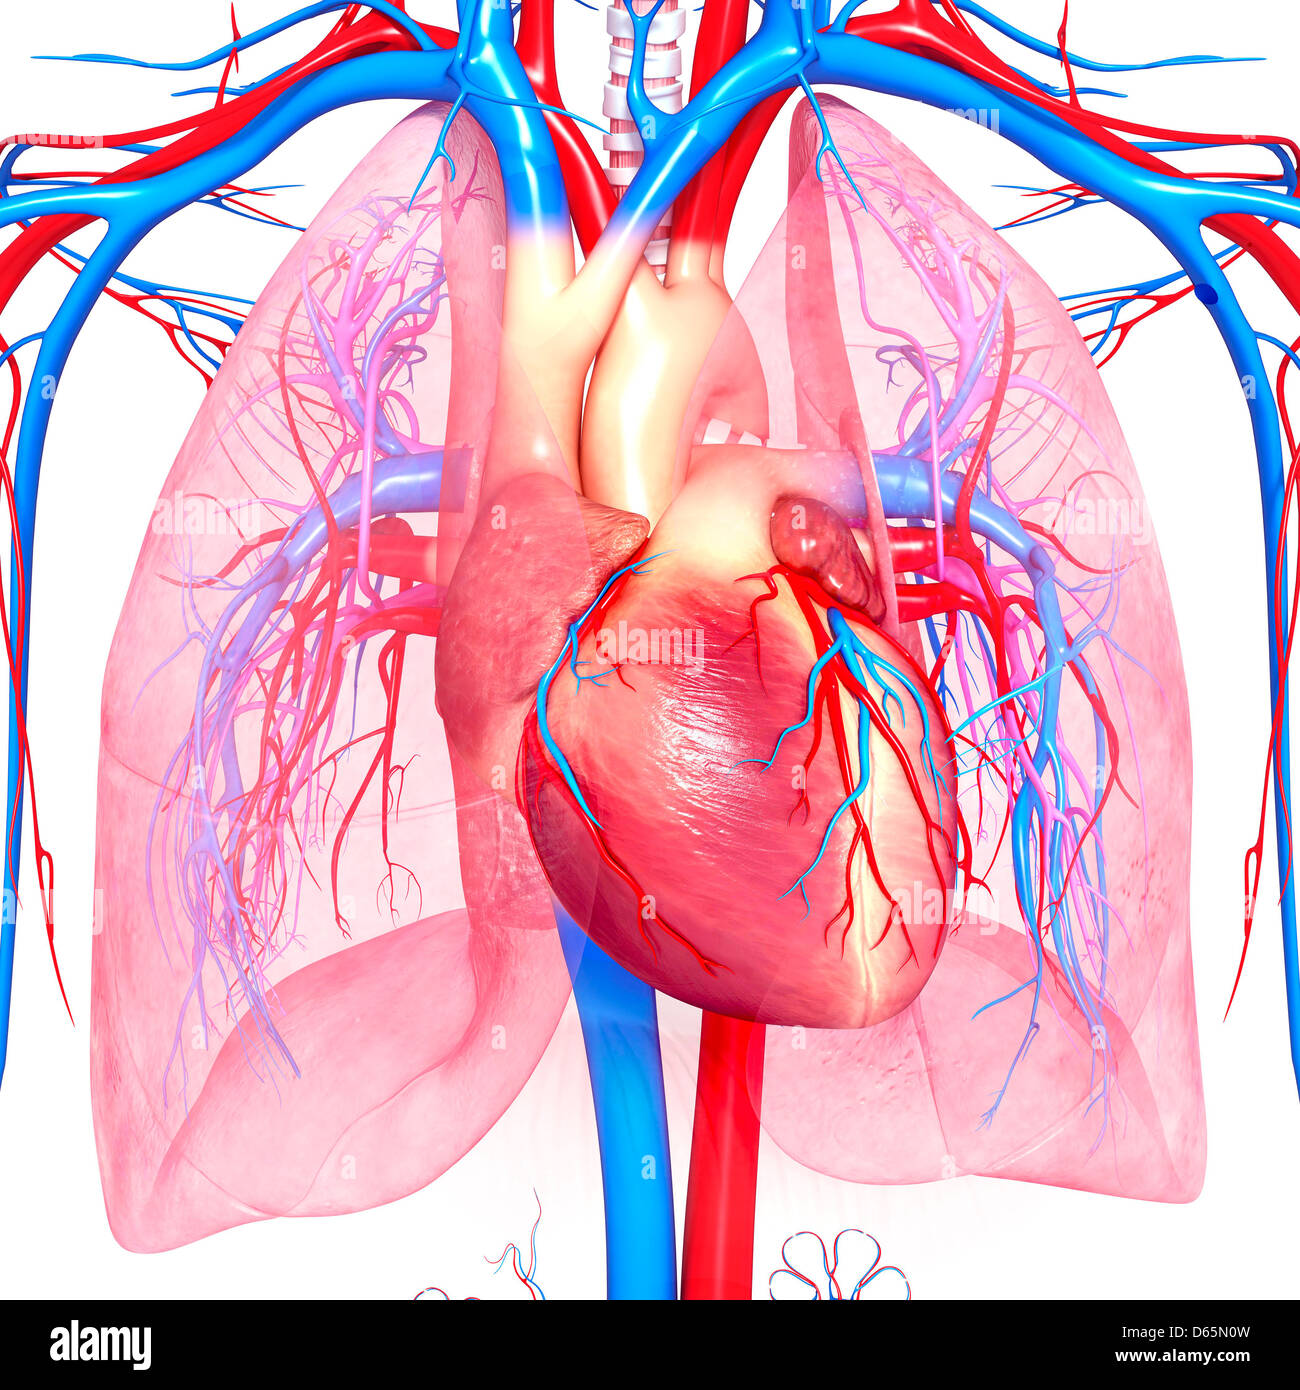

Système cardiovasculaire, artwork